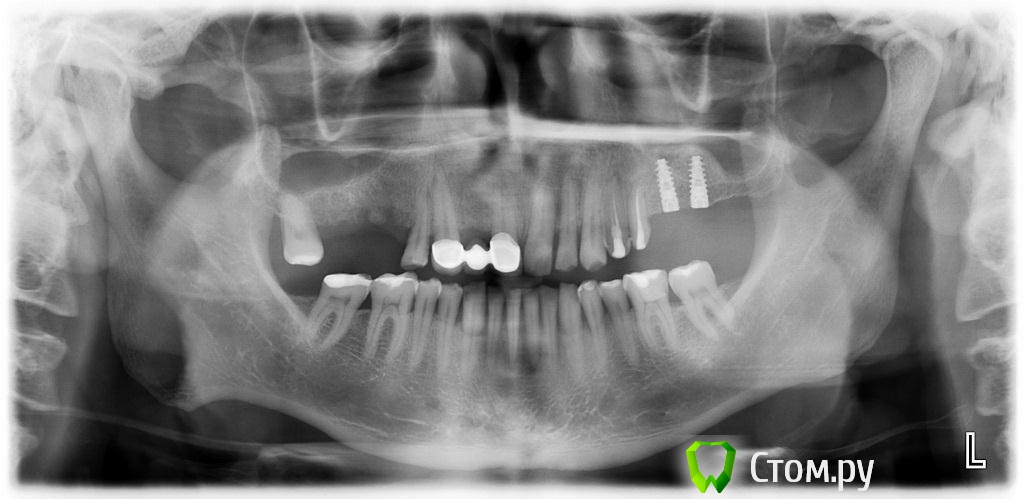

zzkz Опубликовано 1 марта, 2014 Поделиться Опубликовано 1 марта, 2014 (изменено) Первые дни после операци все шло отлично, сегодня при снятии швов обнаружил перфо на одном участке слизистой. Че то я очкую. Не полетит все ??Жалоб нет вообще никаких. Пациент чувствует себя замечтательно. За фото каюсь, пока еще только учусь, вечно не в фокус. Да и в синусах первые шаги(как-то не до фото было) фреза с корейского набора 400$ за набор. очень понравилосьAlfa-bio в обл. 27 зуба - 4.2*11.5; в обл. 26 - 3.65*11.5 + НКР Биоосс, мембрана Альфа Био а вот тут чуть в обморок не упал, мембрана что-ли оголилась. Видать фрезой там зацепил и не заметил, через неделю вылезла собака Ротовые ванночки с 0.05% ХГД и все. сказал ему что все идет по плану, но я то знаю что не так(Не сгниет там все? Изменено 1 марта, 2014 пользователем zzkz Ссылка на комментарий

vesvova Опубликовано 1 марта, 2014 Поделиться Опубликовано 1 марта, 2014 Судя по фото с имплантами ламина там врядли нужна была.Ширины в области шеек достаточно. Да и формирователи скорее всего поставить можно было. Ссылка на комментарий

zzkz Опубликовано 1 марта, 2014 Автор Поделиться Опубликовано 1 марта, 2014 Судя по фото с имплантами ламина там врядли нужна была.Ширины в области шеек достаточно. Да и формирователи скорее всего поставить можно было.это коллагеновая мембрана Альфа био(и правда похожа на ламину). Было НКР в области 26 зуба, тонкий гребень Ссылка на комментарий

Bazbi Опубликовано 16 марта, 2014 Поделиться Опубликовано 16 марта, 2014 Подскажите пожалуйста зачем здесь нужно было проводить нкр? Возле шейки импланта есть по 1-1.5 мм кости на глаз. Импланты spi? Ссылка на комментарий